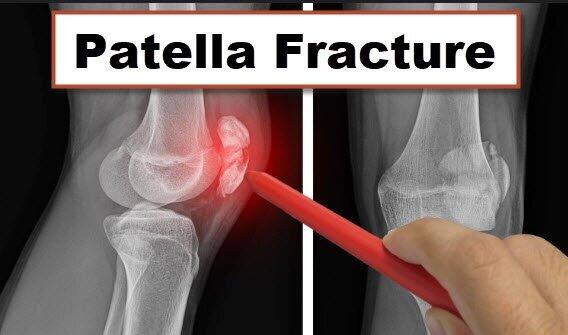

What is Patella Fracture Patella Dislocation

Patella Fractures

Patella Fractures Broken Kneecap of the Knee Knee Specialist

Patellar Fractures Physiopedia

Undisplaced patella fracture Virtual Fracture Clinic